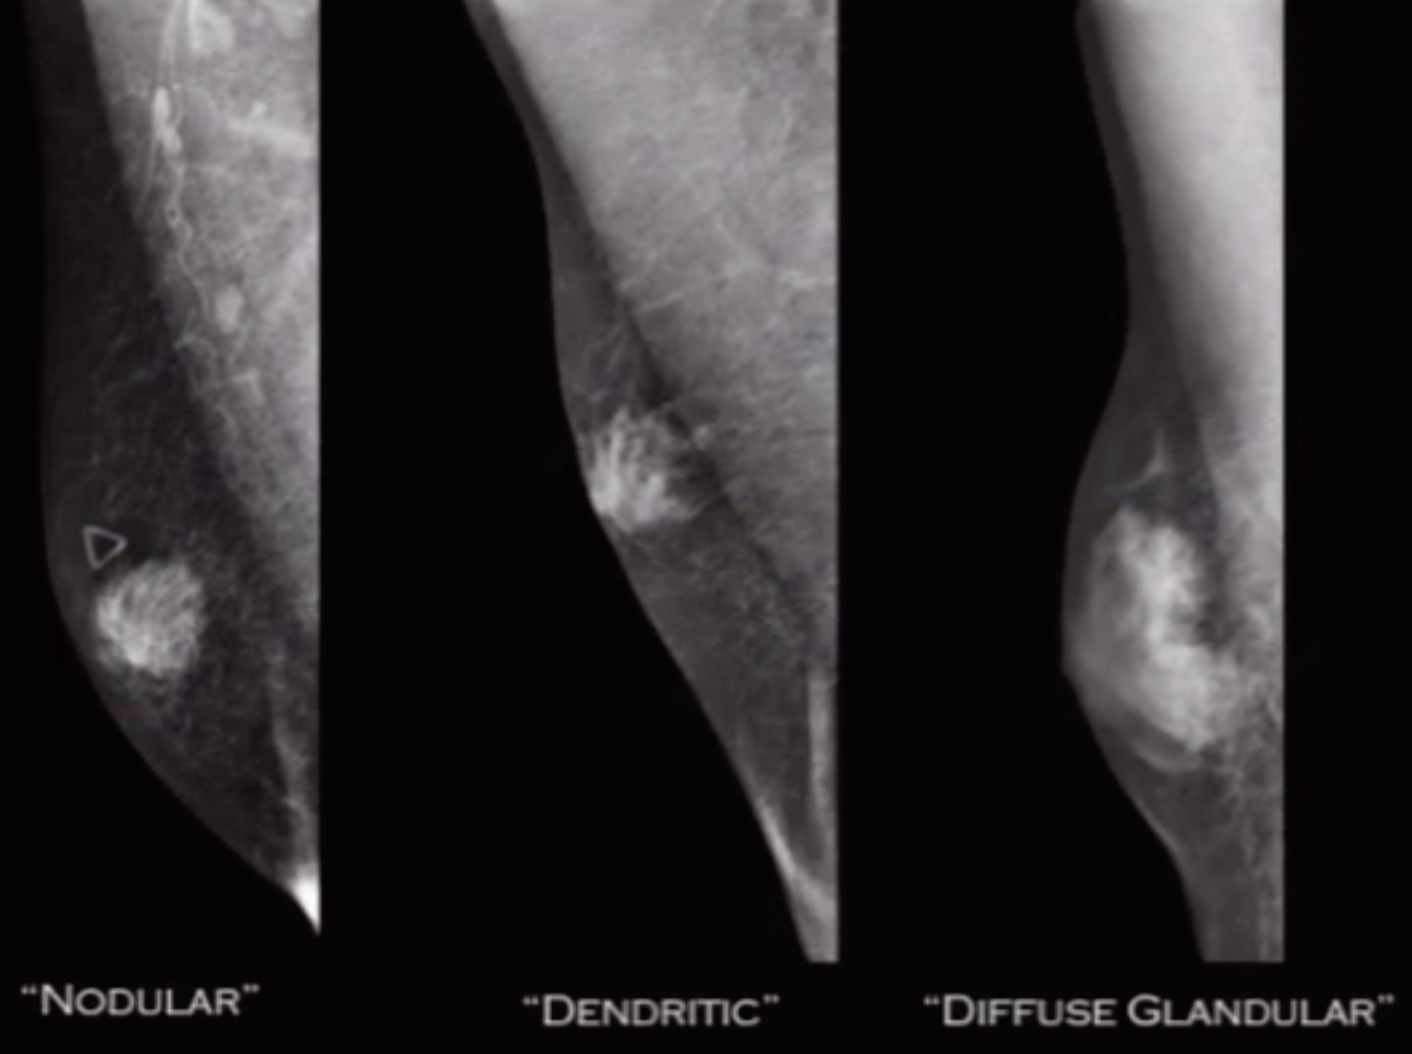

• Types (3)

• Nodular

• Most common

• Retroareolar

• Can be tender

• Stays for a year after initial presentation

• Dendritic

• Chronic fibrotic type

• Non-painful/tender

• Diffuse glandular

• Looks like a woman with small boobs

• Type you get with estrogen therapy